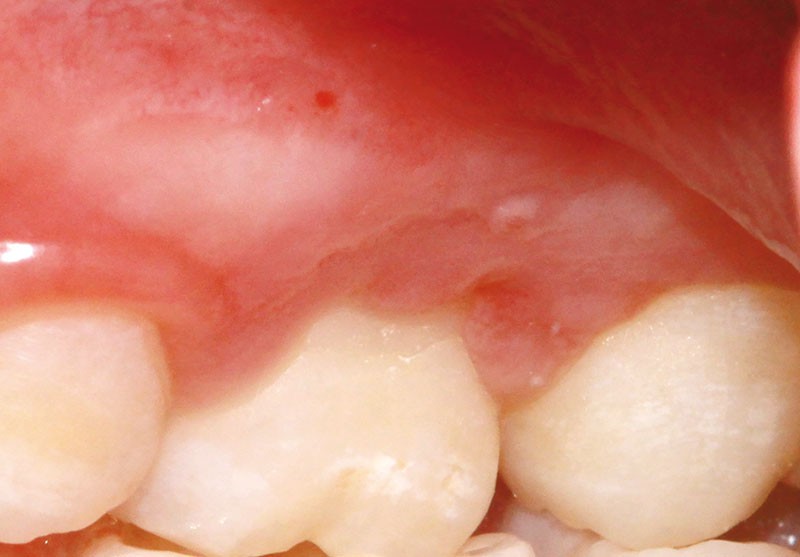

L’examen clinique révèle la présence d’une ulcération végétante, d’environ 1 cm de diamètre, localisée sur les gencives marginale, papillaire et attachée en vestibulaire de 55 et 16, associée à une récession parodontale pour 55. L’ulcération est bien délimitée, indolore et non hémorragique spontanément. Les dents présentent une mobilité physiologique et il n’existe pas d’adénopathie.

Lors du contrôle à une semaine, la situation clinique ne s’est pas améliorée et devant l’aspect…